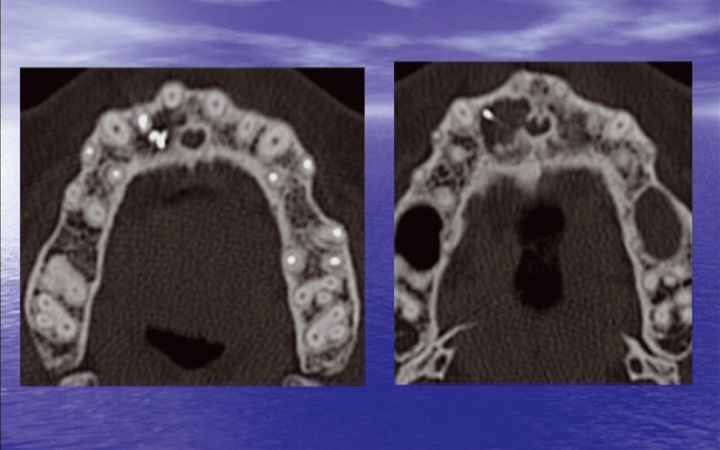

Cas clinique : chirurgie endodontique sur une 12 présentant une lésion apicale étendue en palatin avec destruction de la paroi du canal nasopalatin. HTA stabilisée, bon état général, parodonte fin et sain. Allergie à la pénicilline Matériels et matériaux : microscope opératoire Zeiss, inserts ultrasonores, curette de Lucas, IRM®, Astringedent ®, Vicryl®, kit Endo Success Apical Surgery® Satelec, Fraise Prisma, micro-moteur Chiropro (BienAir)

Résumé en images :